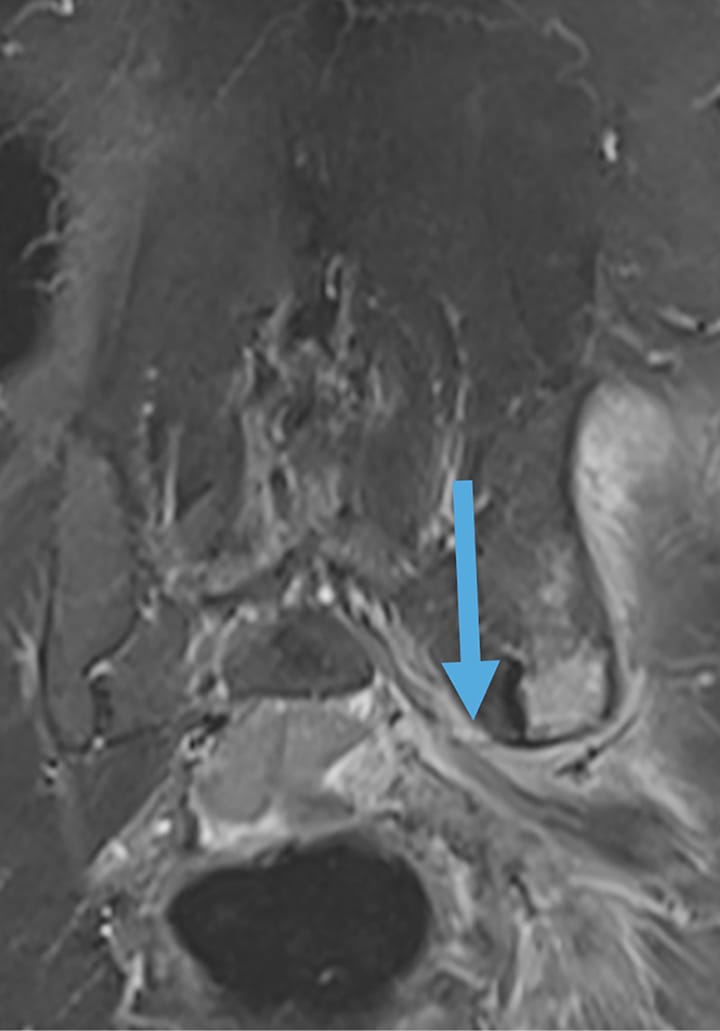

Imagerie Métastase osseuse avec extension dans le canal sous-piriforme avec irritation du nerf sciatique